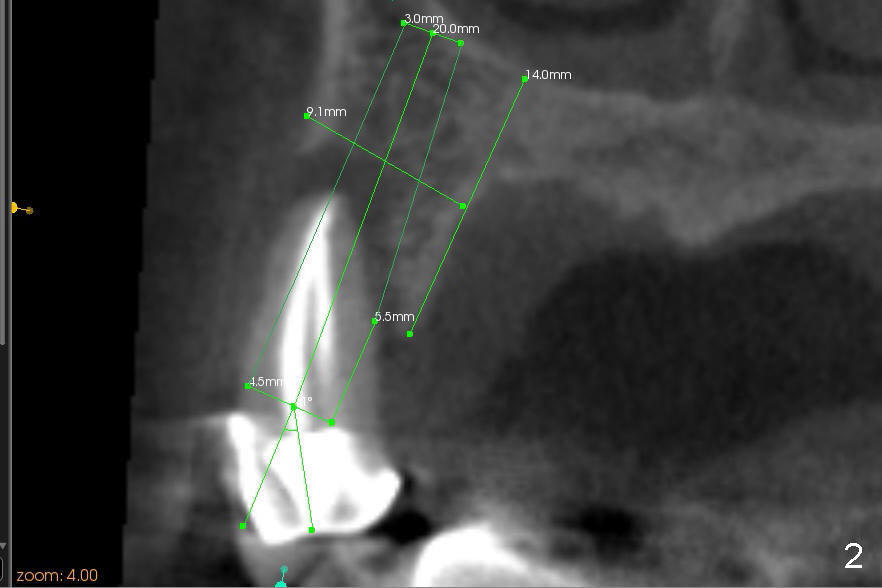

The radiolucency is more or less confined to the apical region. The fistula is most likely due to endo failure. The buccal and lingual canals fuse before exit. Debridement and filling were not done properly. Although root canal retreatment is an option, implant replacement offers long term prognosis.

It appears that there is a buccal bony defect coronally. The implant is placed more or less palatally (in position and tilt) for better restoration. Either bone level (4.5x14 mm, Fig.1) or tissue-level (4.5x20, Fig.2) implant is placed. The diameter is more or less determined by the adjacent teeth (Fig.3). A 4.5x14 mm bone level implant should obtain sufficient primary stability (Fig.4). If not, either the diameter or length of the implant is to be increased.